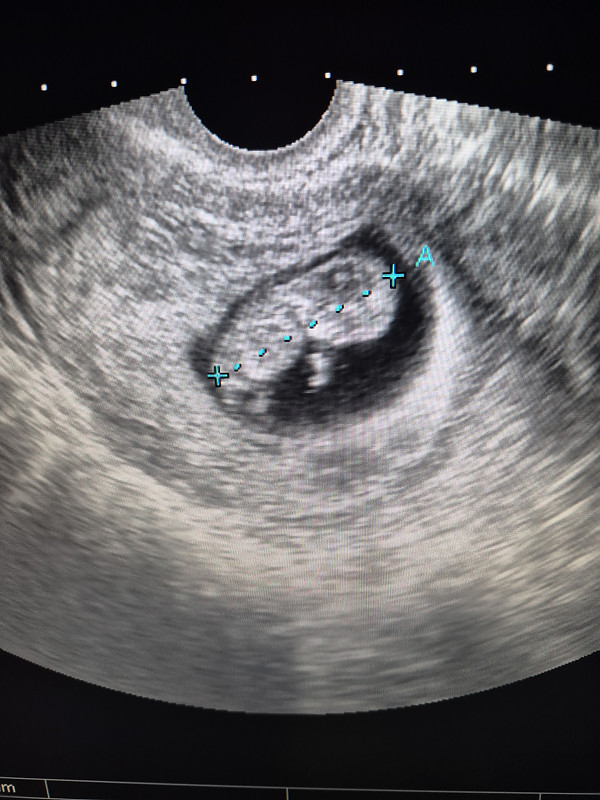

Sveikos. Grįžtu su savo stebuklu! Prieš 2 savaites buvo nustatytas nesivystantis ir laukėm persileidimo. Šiandien nueinu pas gydytoją, kad niekaip neprasideda persileidimas. Pažiūri su echo, o ten širdelė plaka!

Sveikos. Grįžtu su savo stebuklu! Prieš 2 savaites buvo nustatytas nesivystantis ir laukėm persileidimo. Šiandien nueinu pas gydytoją, kad niekaip neprasideda persi…

Apsilankymo metu buvo beveik 10sav.širdelė plaka, sako viskas gerai 🙂